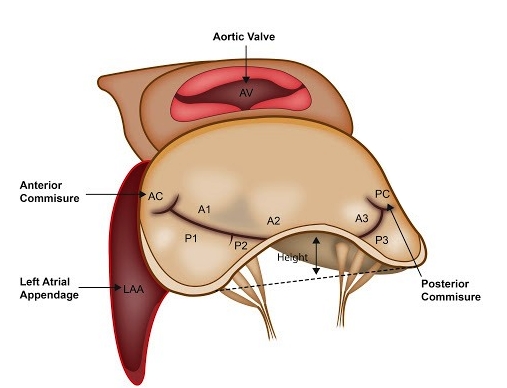

O anel mitral é uma estrutura fibrosa complexa em formato de sela que faz parte do aparato valvar atrioventricular esquerdo,…